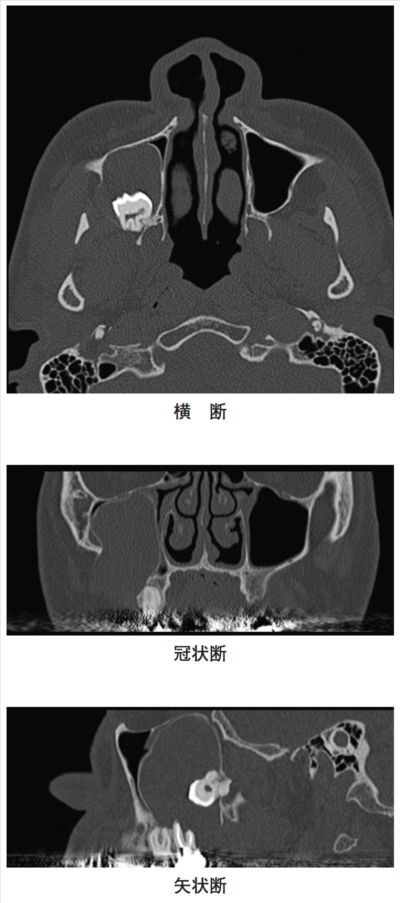

25歳の女性。顔面部の腫脹を主訴として来院した。右側の頰部に無痛性の腫脹を認める。初診時の横断、冠状断および矢状断の骨表示CTを別に示す。

病変が接するのはどれか。2つ選べ。

a. 眼窩底

b. 鼻中隔

c. 頰骨弓

d. 篩骨洞

e. 鼻腔側壁